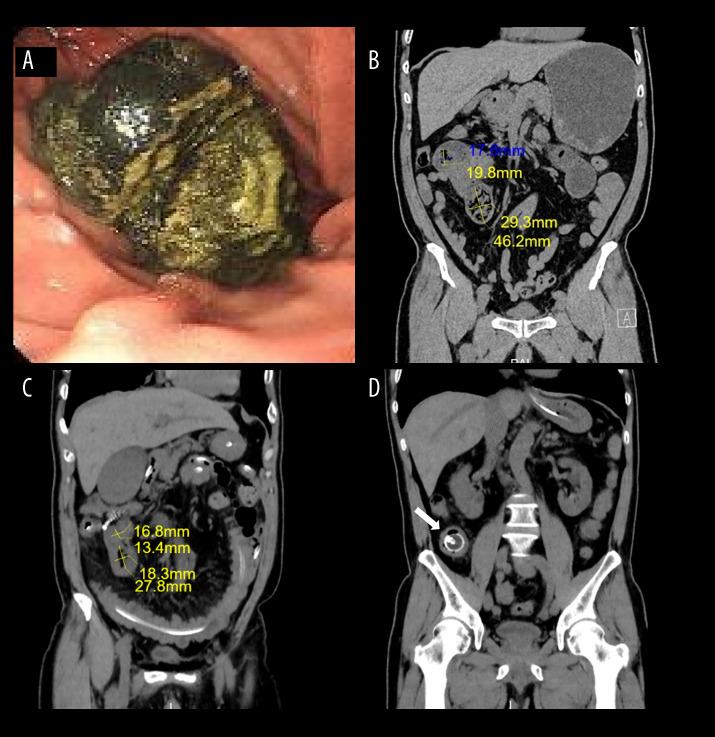

BACKGROUND Phytobezoar-induced small bowel obstruction presents significant management challenges, particularly in patients who either decline surgery or have contraindications. These concretions, predominantly composed of persimmon tannins, account for 0.4-4.8% of intestinal obstructions in endemic regions. While surgical intervention remains standard for complete obstructions, non-surgical approaches are increasingly explored for high-risk patients. Current dissolution therapies, including the Coca-Cola protocol, often require large fluid volumes that can exacerbate the obstruction. This study evaluated the efficacy of a novel treatment using low-volume sodium bicarbonate irrigation combined with catheter decompression. CASE REPORT Two elderly men (aged 73 and 74 years) with persimmon-induced obstructions refractory to conservative treatment underwent endoscopic intestinal catheter placement. Targeted 5% sodium bicarbonate irrigation (100 mL bid) with intermittent catheter clamping was administered. Clinical progress was monitored through serial imaging and symptom assessment. Both cases achieved complete obstruction resolution without surgery. Case 1 demonstrated CT-confirmed bezoar reduction within 10 days, with spontaneous passage. Case 2 expelled a 3×7 cm bezoar after 5 days of therapy. No procedural complications or biochemical imbalances occurred. The protocol synergized bicarbonate's mucolytic action (alkaline dissolution of phytobezoar matrices) with mechanical catheter decompression. CONCLUSIONS This first-reported combination therapy successfully resolved large phytobezoars (4-7 cm) within 5-10 days, establishing a safe alternative for candidates who either decline surgery or have contraindications. The method's efficacy stems from: 1) minimized fluid volume requirements (200 mL/day vs 500-3000 mL in Coca-Cola protocols), 2) direct bezoar contact via catheter-directed delivery, and 3) dual mechanical-chemical action.